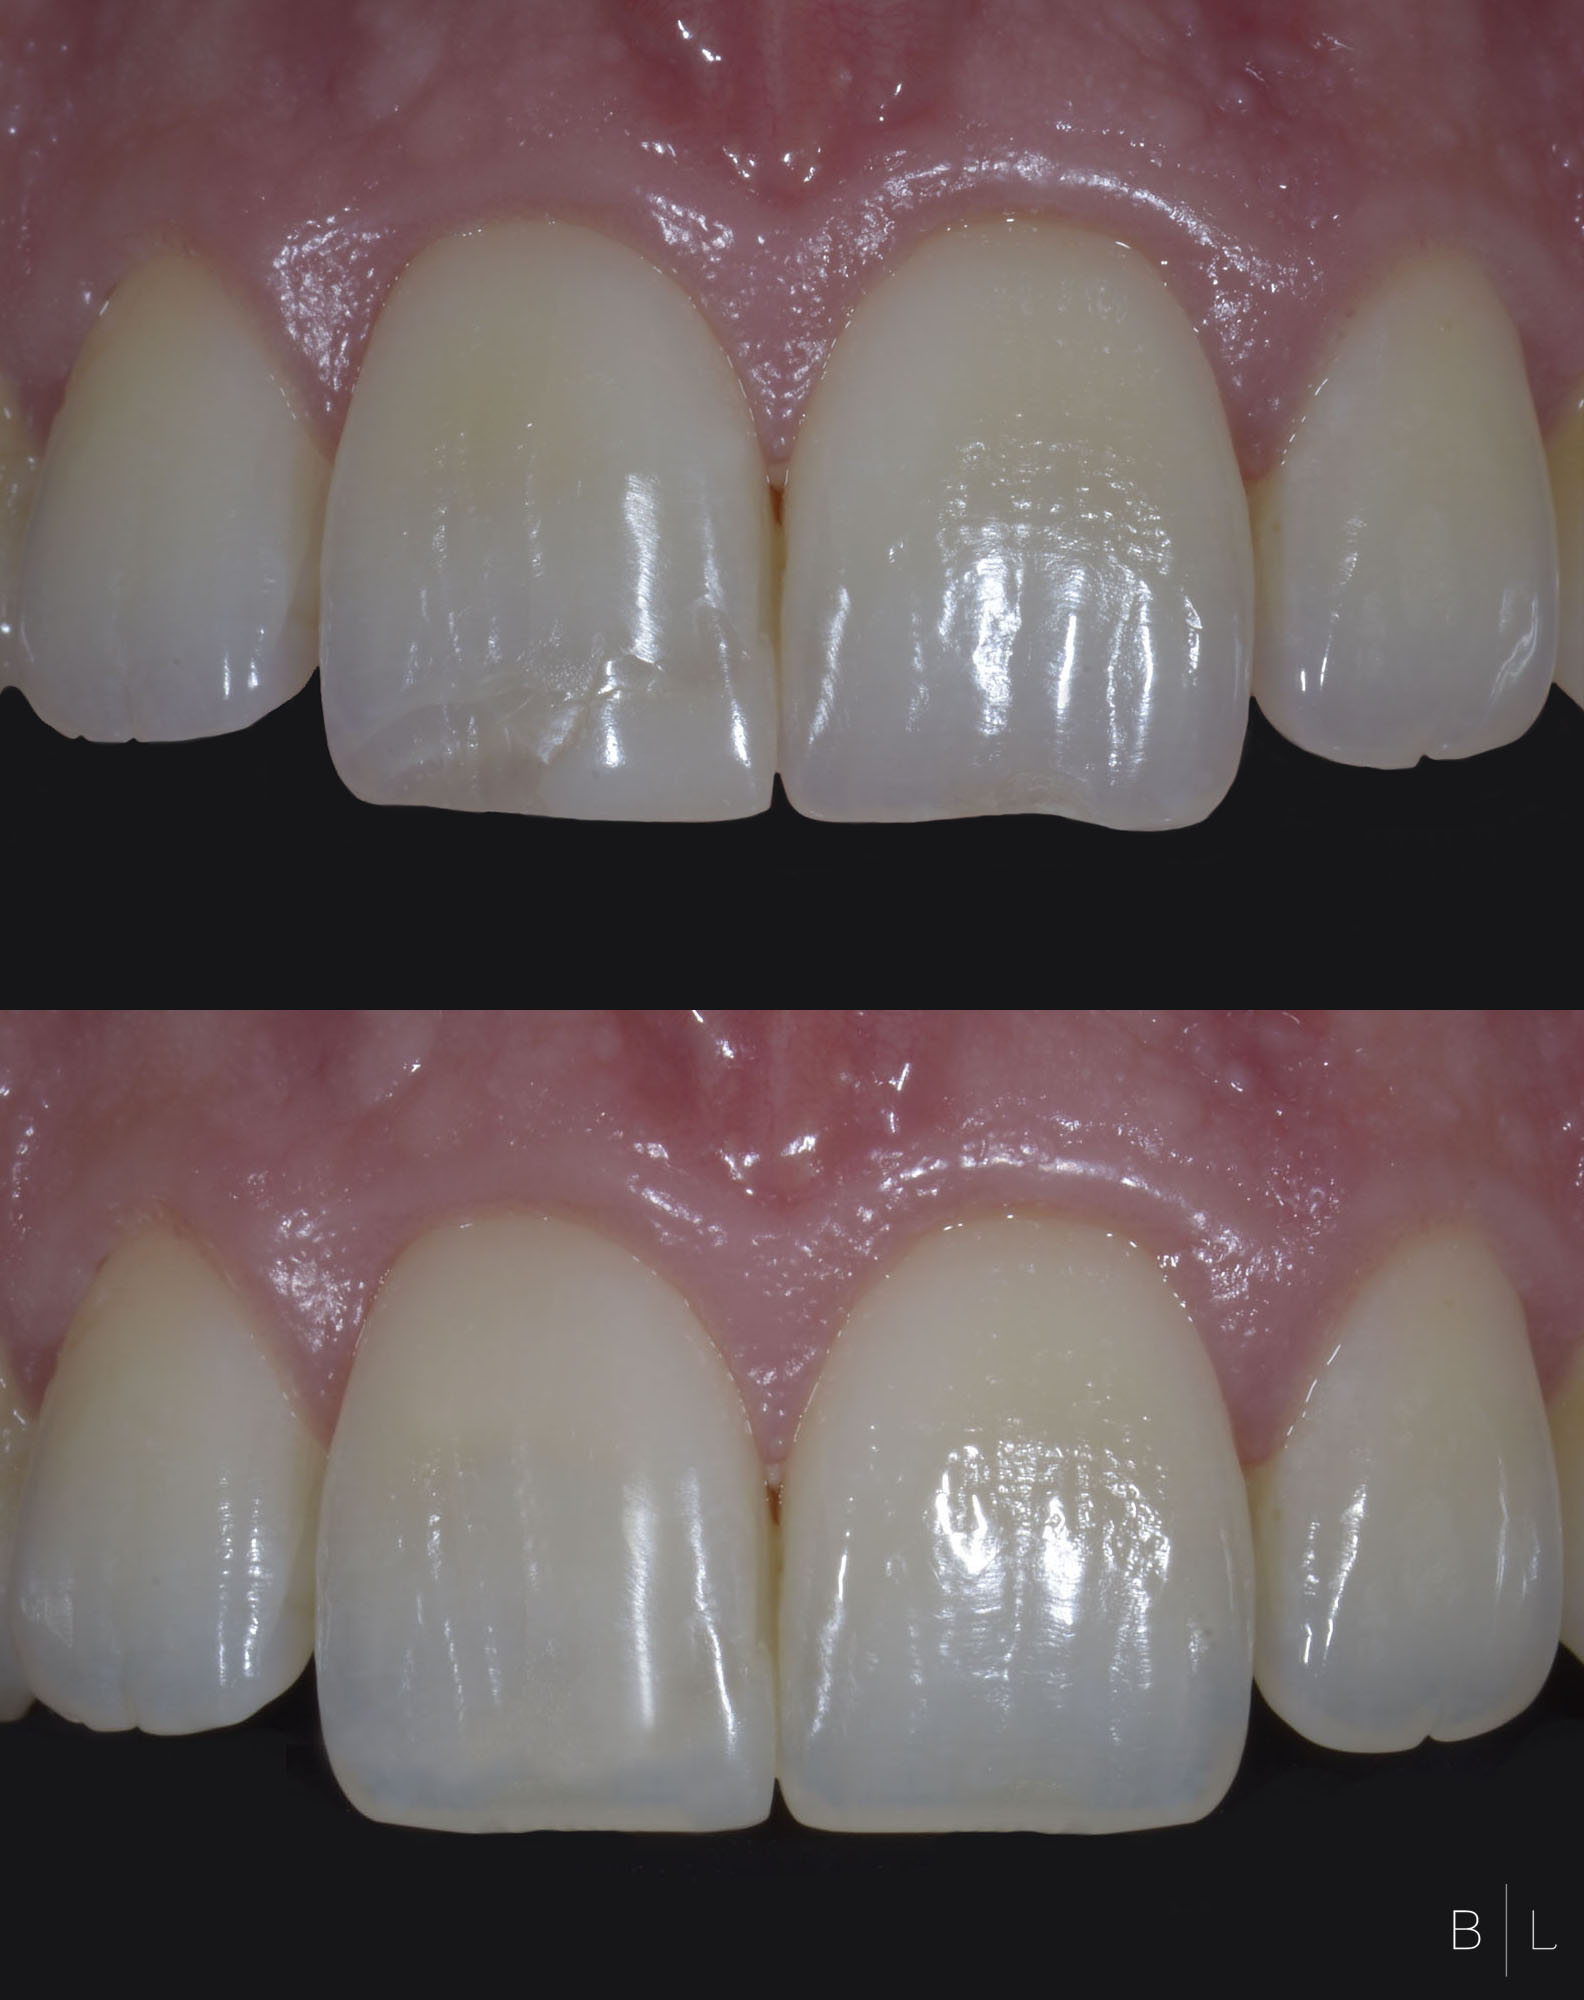

Facettes 11-21